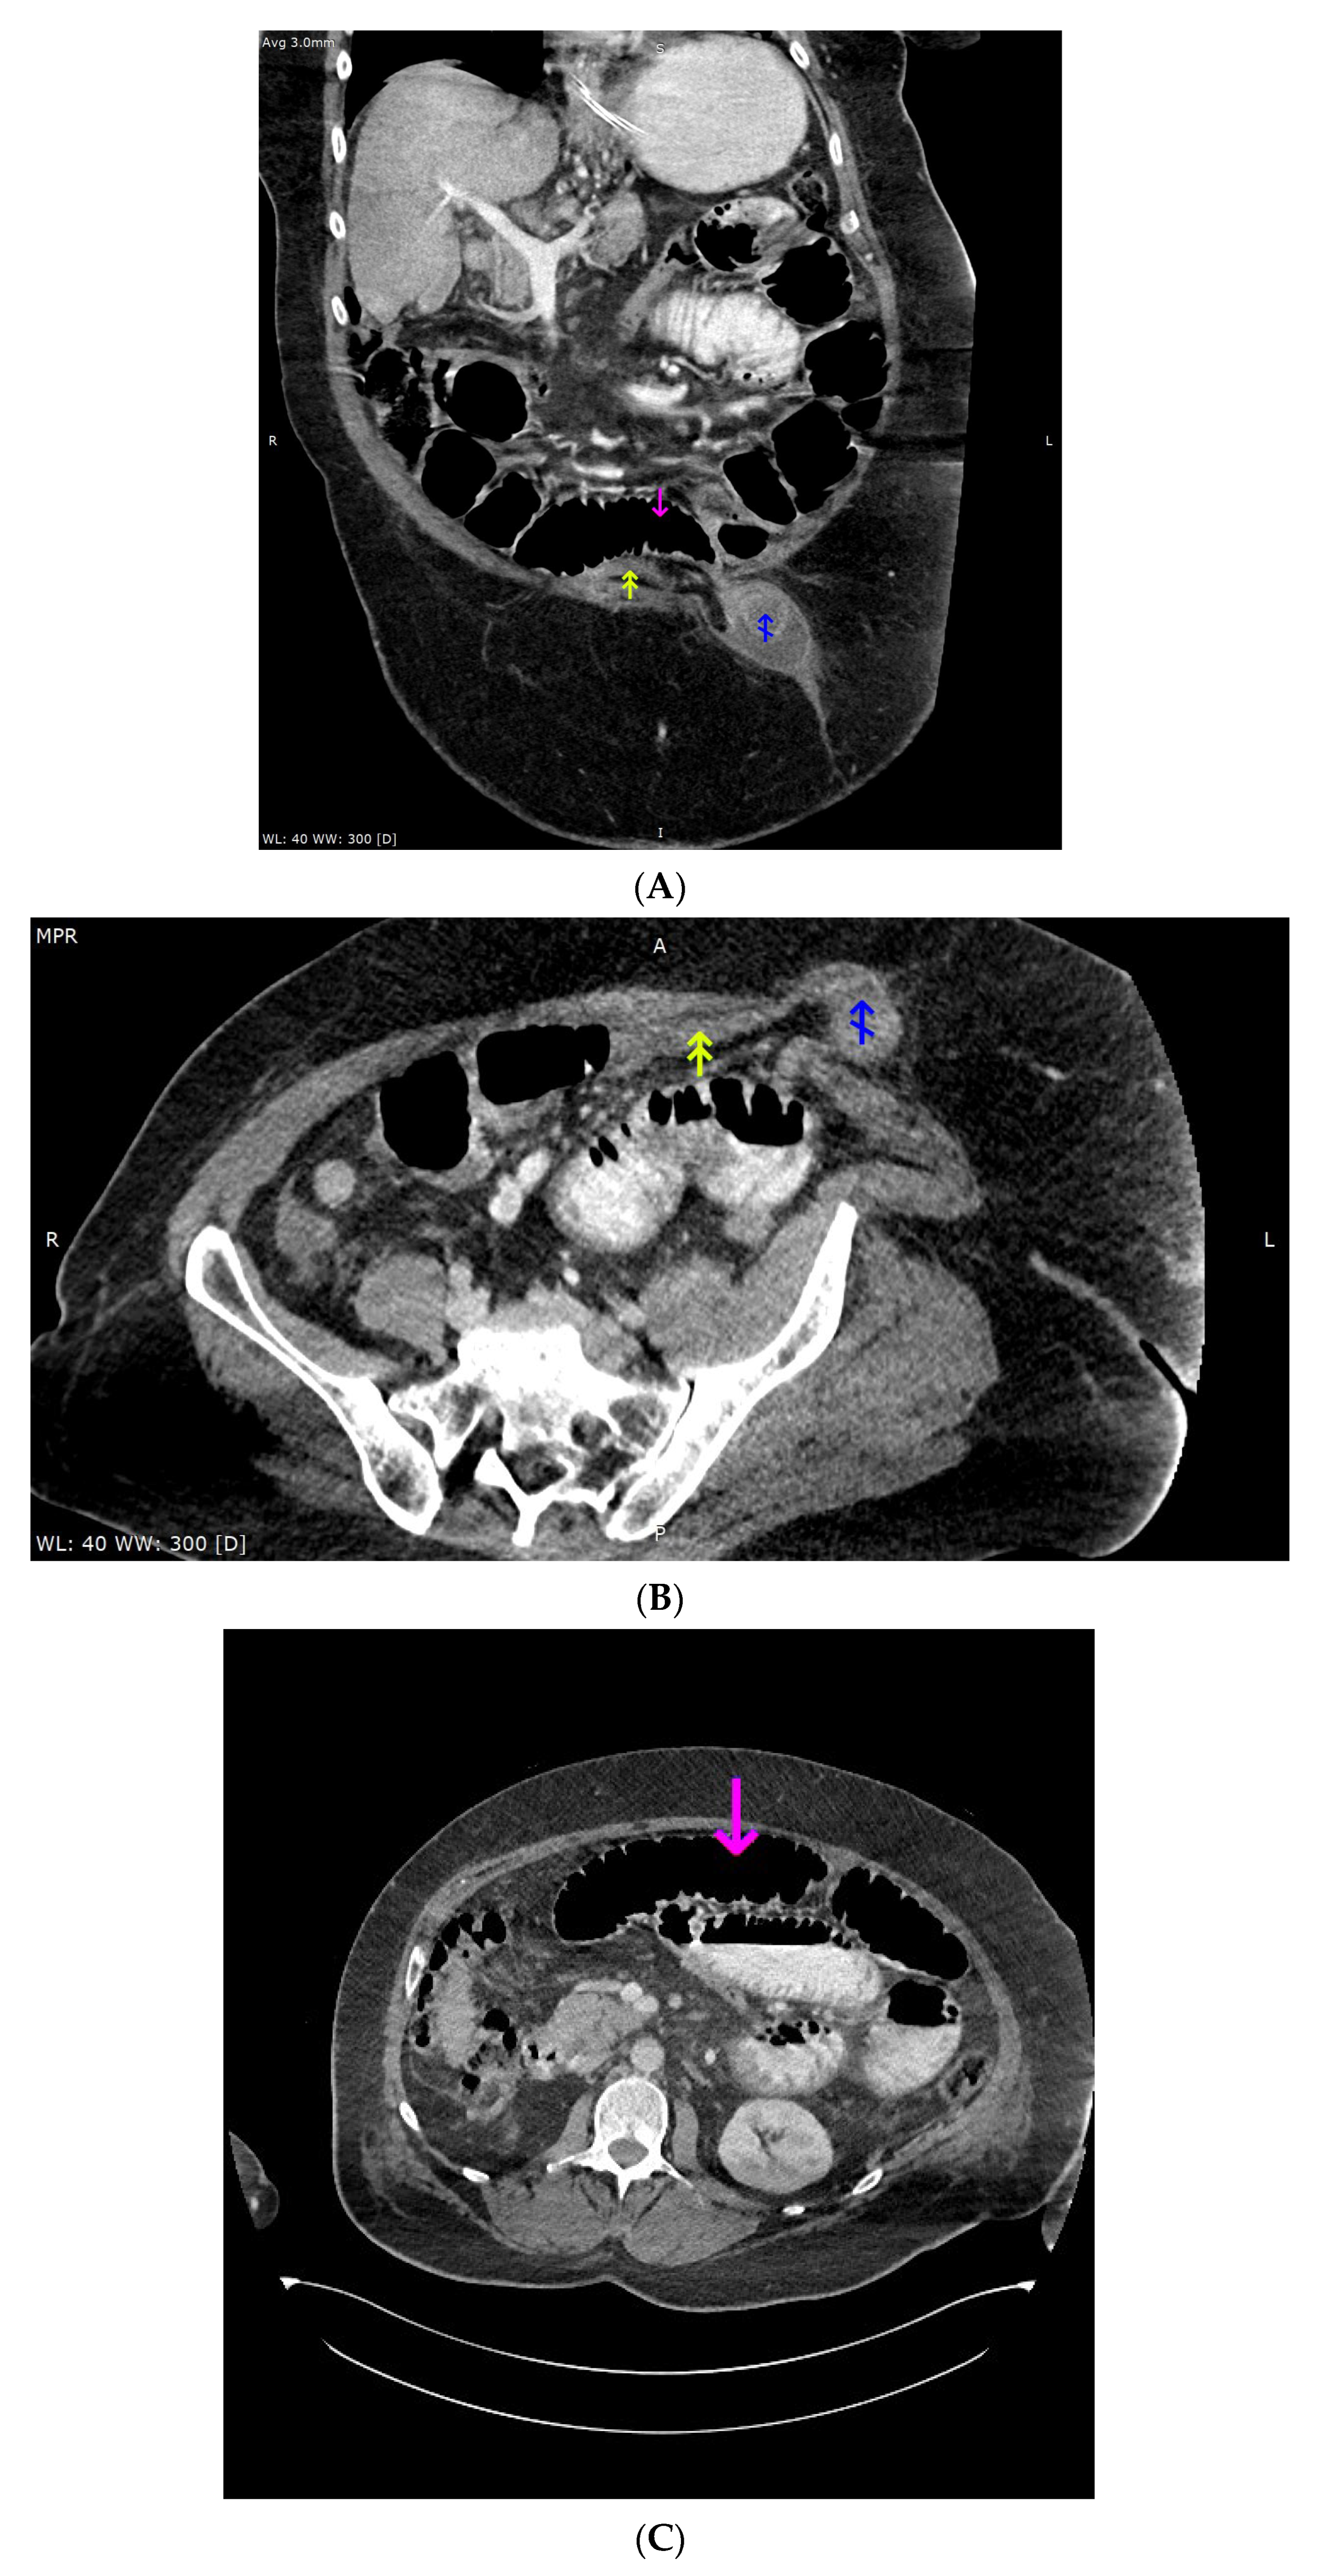

Due to history of umbilical hernia, computed tomography (CT) of the abdomen and pelvis was performed and showed radiographic signs of mechanical bowel obstruction with dilation of jejunum and ileum proximal to the hernia (Figure 2A–C).

Figure 2.

(A) Computed tomography imaging of the abdomen and pelvis, portal-venous phase, oral contrast administered, oblique (closest to coronal) reconstruction (3 mm). Magenta arrow points to the pre-stenotic, dilated small intestine, lumen mostly filled with gas; double yellow arrow points to the post-stenotic, small intestine without any content; blue arrow points to the edematous small intestine loop inside the hernia sac, surrounded by fluid; (B) Computed tomography imaging of the abdomen and pelvis, portal-venous phase, oral contrast administered, oblique (closest to axial) reconstruction (3 mm). Double yellow arrow points to the post-stenotic, small intestine without any content; blue arrow points to the edematous small intestine loop inside the hernia sac, surrounded by fluid. (C) Computed tomography imaging of the abdomen and pelvis, portal-venous phase, oral contrast administered, axial reconstruction (1.5 mm). Magenta arrow points to the pre-stenotic, dilated small intestine, lumen mostly filled with gas.

The patient underwent emergency resection of the intussuscepted ileum. The intussusception of the small intestine was described previously a cause of acute-on-chronic liver failure [3,4]. Due to high ammonia concentration and status post intestinal surgery with potential for further ammonia increase, a series of single-pass albumin dialysis (SPAD) procedures was performed. The ammonia concentration decreased with successive SPAD procedures to 252, 100, and 98 µg/dL. The patient died from multi-organ failure.